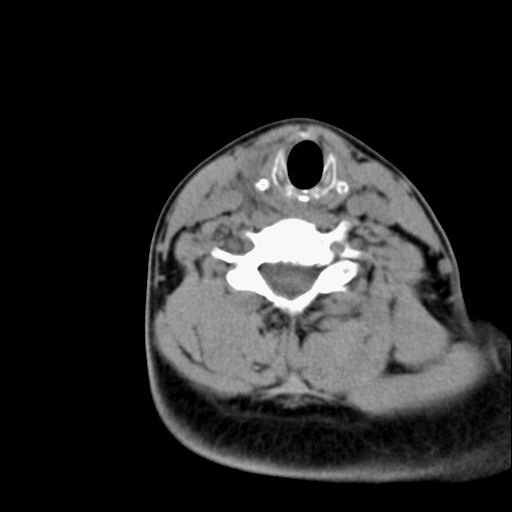

标题: CT23947 右颈部触及00.5x1.5cm质硬长形肿块,疼痛 [打印本页]

标题: CT23947 右颈部触及00.5x1.5cm质硬长形肿块,疼痛

右侧甲状腺病灶,建议增强或结合b超检查。

甲状腺右叶占位病变,建议增强扫描。

甲状腺占位  定性有时很难 但无论癌还是腺瘤 还是手术比较好!以下是甲状腺占位的ct鉴别诊断

确定病变范围,判断有无部属淋巴腺转移,甲状腺肿物没有可靠的征象鉴别良、恶性,如有部属淋巴结肿大、喉返神经麻痹、甲状软骨或其它喉软骨破坏等表现,则有利于诊断恶性。钙化不是鉴别良、恶性的依据。

ct表现:形态不规则的软组织密度肿块,可累及部分或大部分甲状腺组织,密度不均,可坏死、囊变、钙化,增强病灶呈不均匀强化,有局部侵犯或转移时可有颈部淋巴结肿大。

ct表现肿瘤呈稍低密度结节状肿块,边缘光整、锐利病灶均匀强化,少数腺瘤可有钙化。

甲状腺右侧叶占位,定性困难,建议增强。

右侧甲状腺低密度病灶,性质待定;建议行进一步检查。